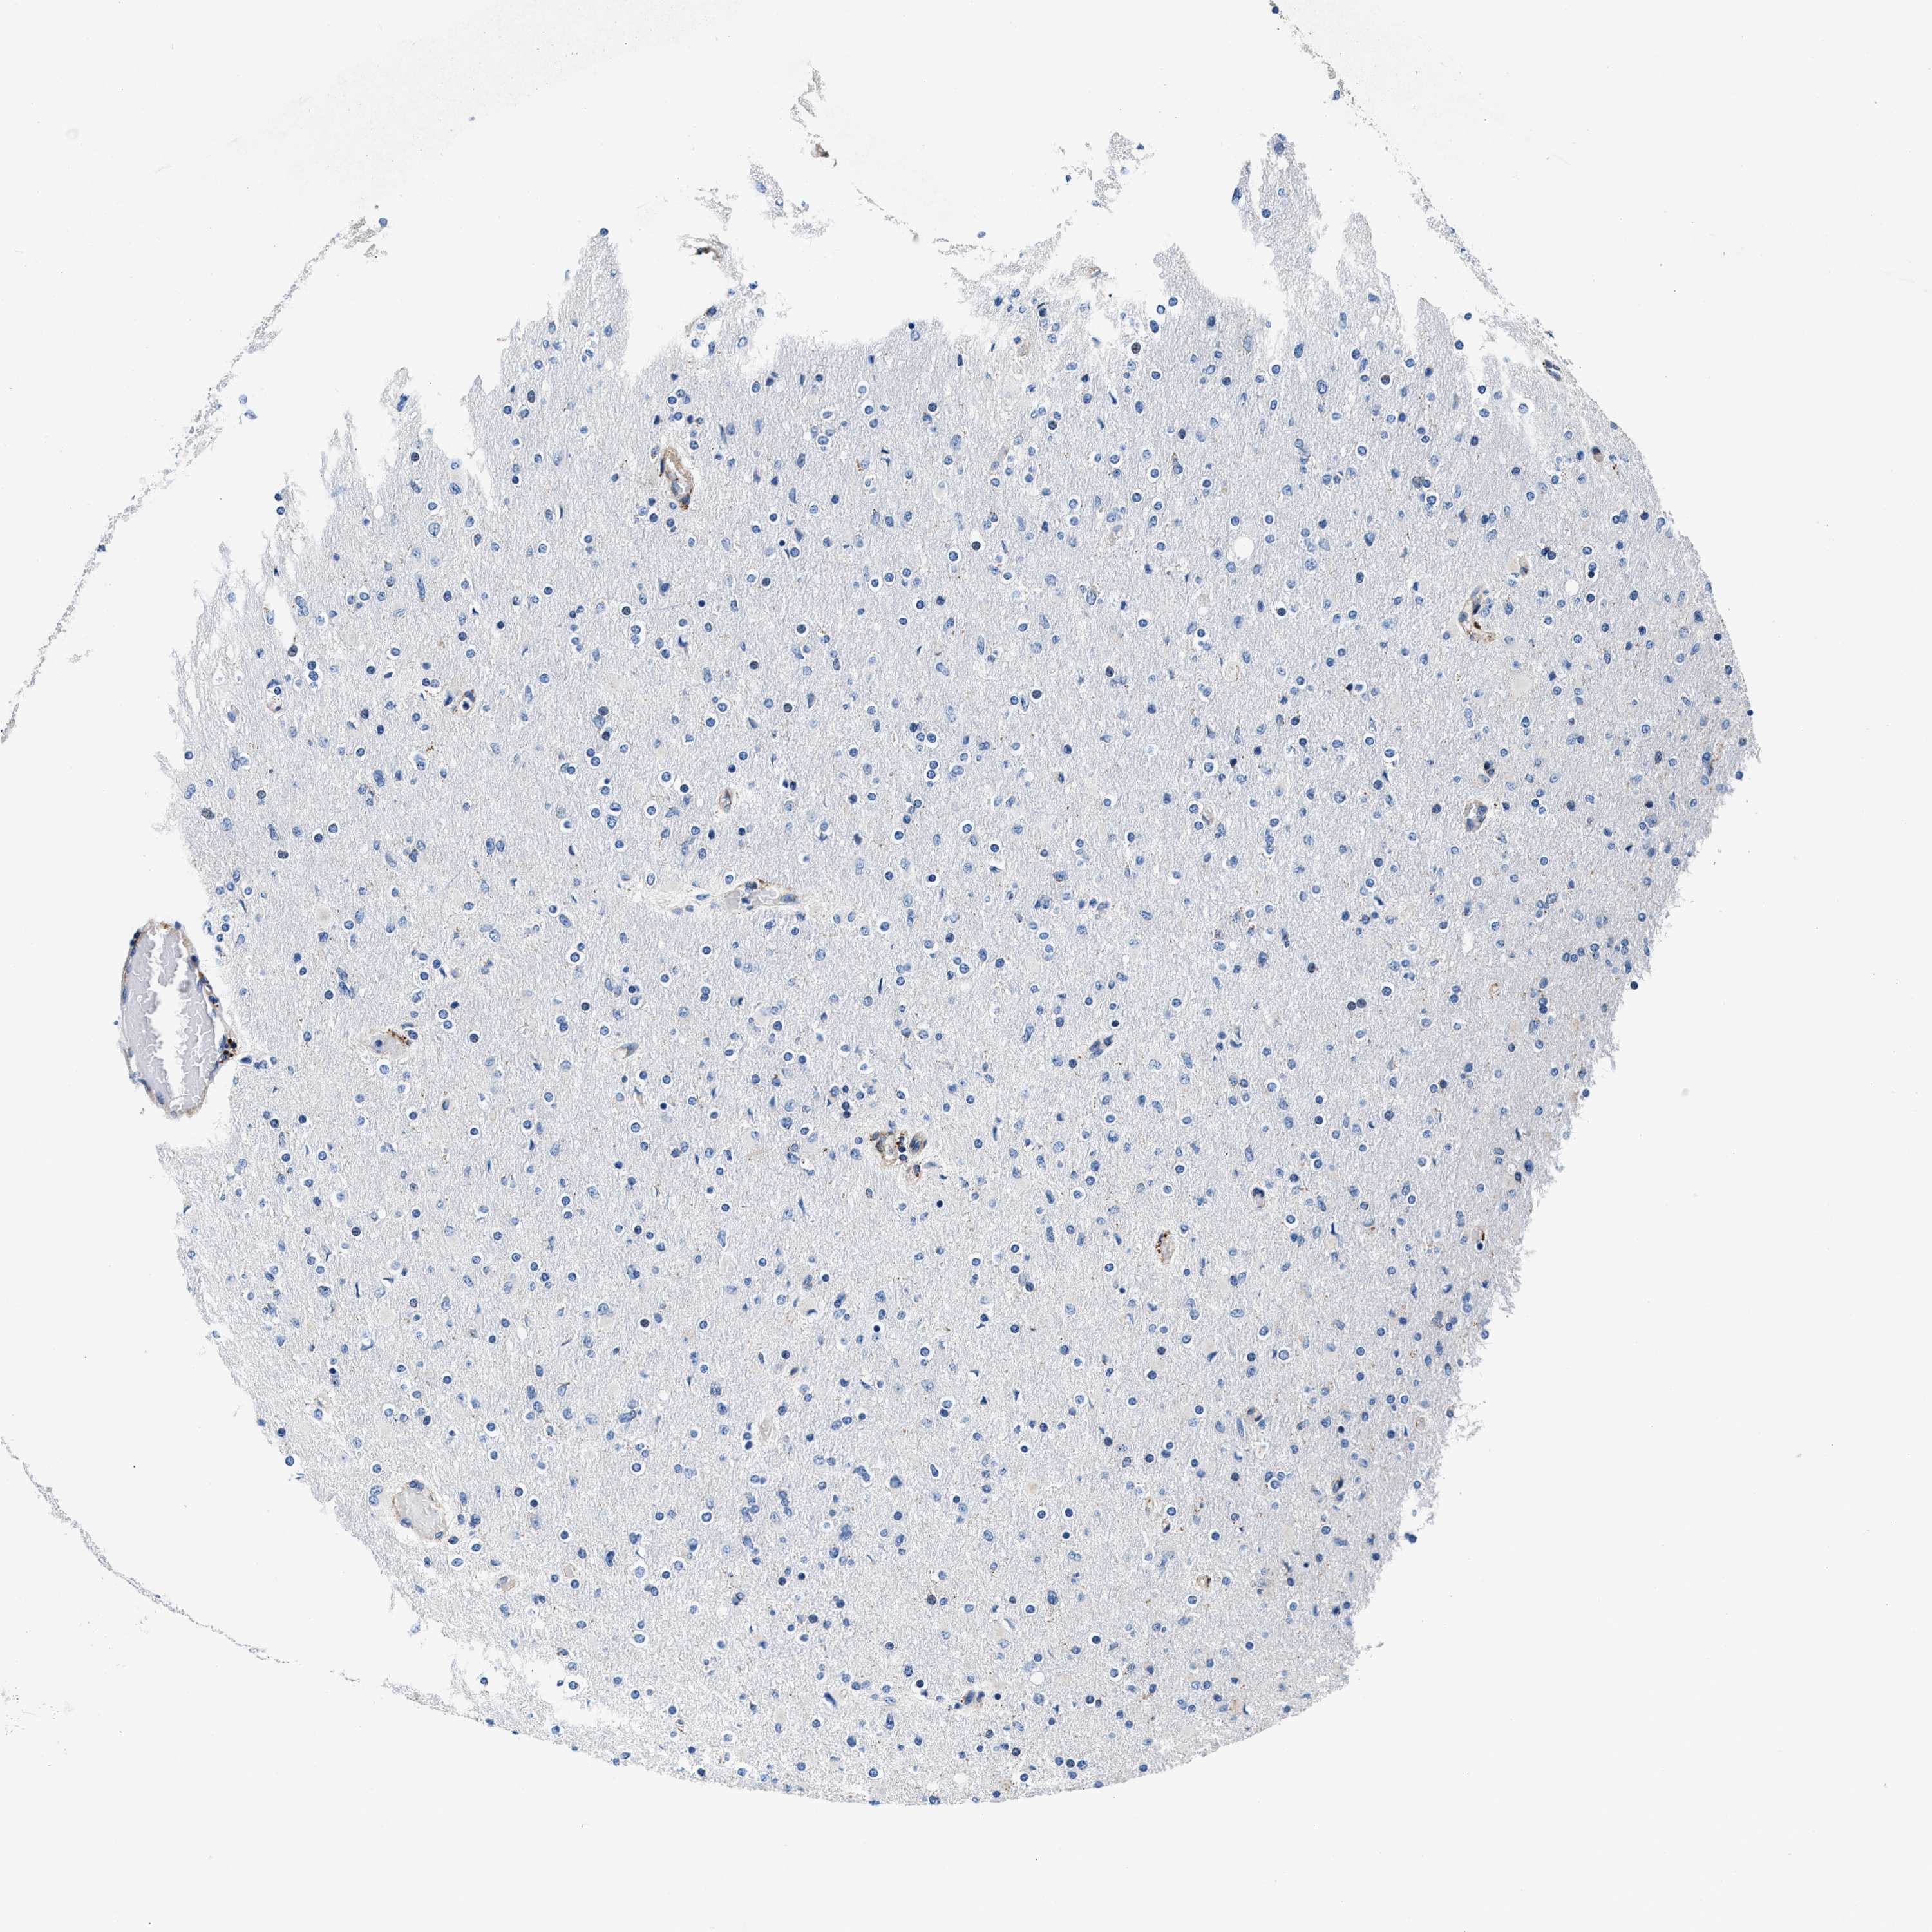

GLIOMA - Protein expressioni

A mouse-over function shows sample information and annotation data. Click on an image to view it in a full screen mode. Samples can be filtered based on level of antibody staining by selecting one or several of the following categories: high, medium, low and not detected. The assay and annotation is described here.

Note that samples used for immunohistochemistry by the Human Protein Atlas do not correspond to samples in the TCGA dataset.

Antibody stainingi

Antibody staining in the annotated cell types in the current human tissue is reported as not detected, low, medium, or high, based on conventional immunohistochemistry profiling in selected tissues. This score is based on the combination of the staining intensity and fraction of stained cells.

Each image is clickable and will lead to virtual microscopy that enables deeper exploration of all samples and also displays staining intensity scores, fraction scores and subcellular localization as well as patient and tissue information for each sample.

Antibody CAB001960

Antibody CAB016353

Staining

High

Medium

Low

Not detected

Intensity

Strong

Moderate

Weak

Negative

Quantity

>75%

75%-25%

<25%

None

Location

Nuclear

Cytoplasmic/membranous

Cytoplasmic/membranous,nuclear

Glioma, malignant, High grade

Glioma, malignant, Low grade